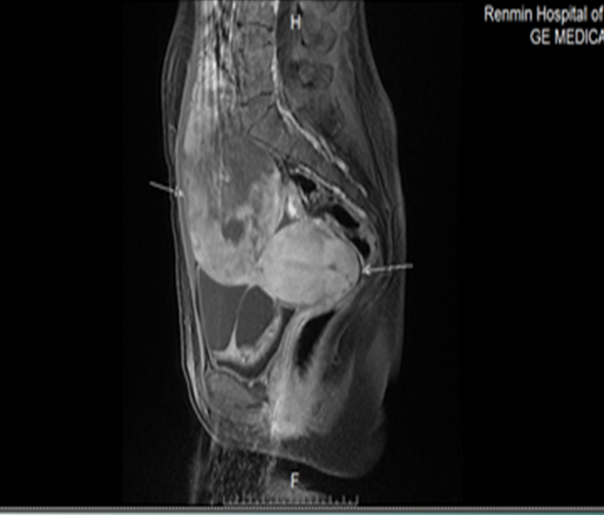

盆腹腔MRI(2018090900826)提示:1.下腹腔及盆腔内巨大囊实性肿块,考虑卵巢肿瘤性病变;2.子宫未见异常,宫颈腺囊肿;3.盆腔少量积液。

MRI特点 :